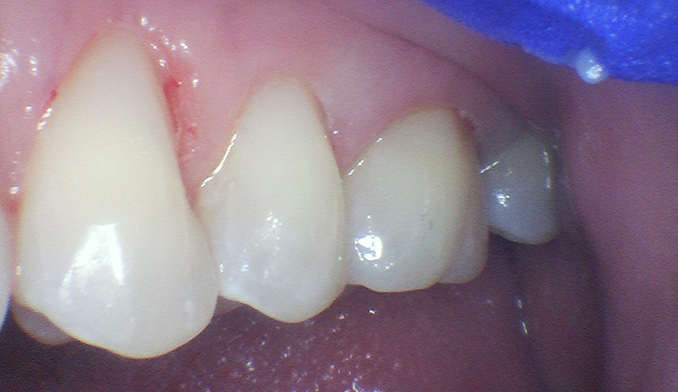

Gumline Bonding for Esthetics and Protection

The patient requested bonding along the gumline to improve appearance and protect exposed areas. We placed tooth-colored fillings to restore a smooth, natural look and enhance long-term oral health.